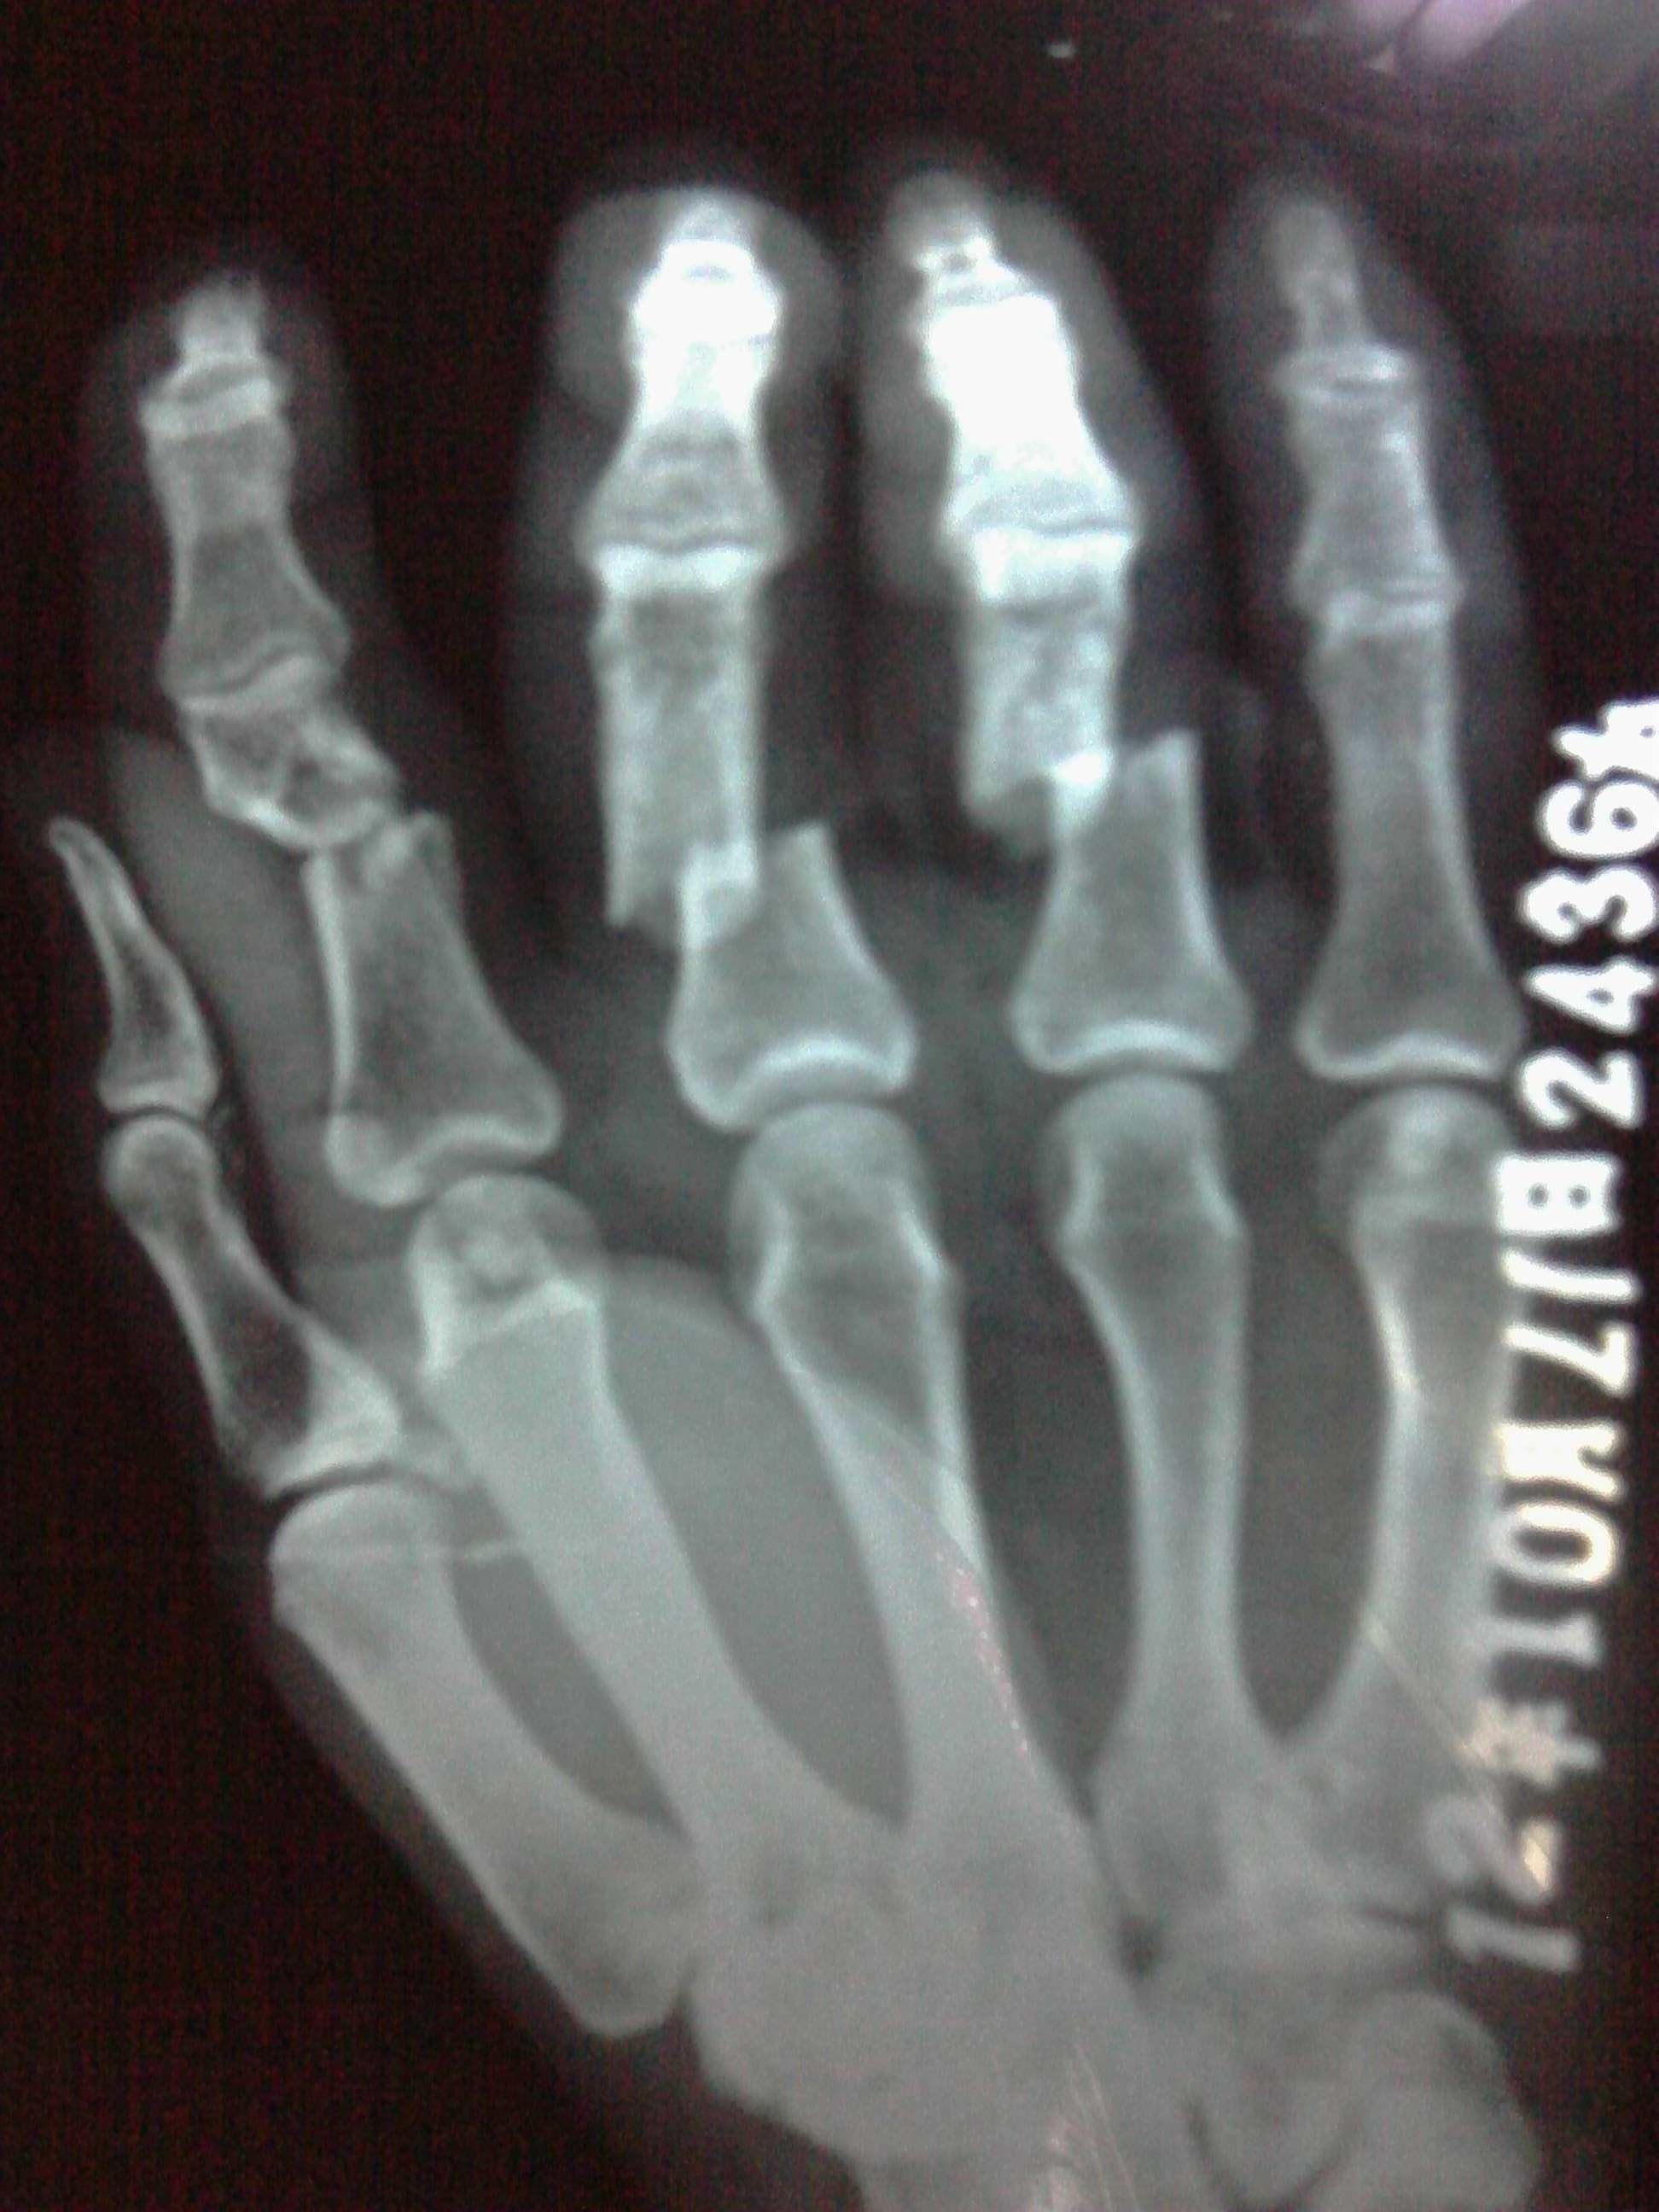

按照你的片子,应该是骨折加钢针固定治疗,基本符合工伤九级。具体看功能影响情况,甚至可以达到更高级别。

没有伤到大拇指关节,最多9级,毫无悬念。严格的来讲,评上10级你就应该庆幸了。